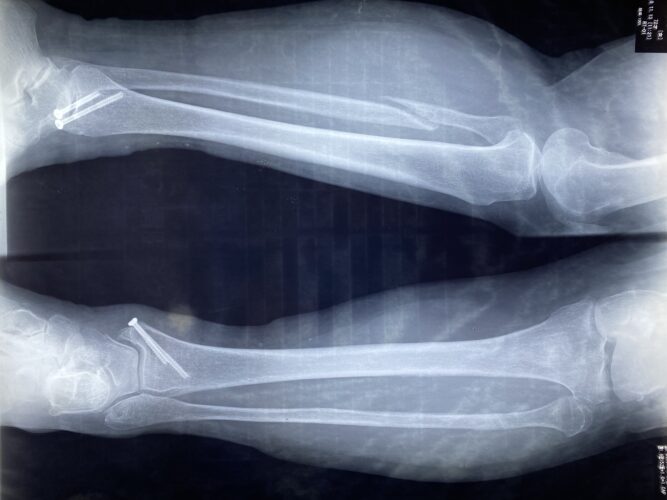

第25回整骨研究会「賜恩」研修会開催

春日部市市民活動センター(前腕骨骨幹部骨折)

第26回整骨研究会「賜恩」研修会開催